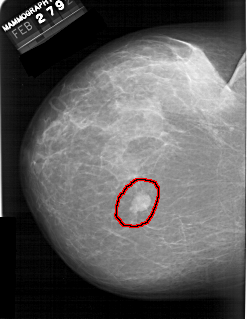

A_1389_1.LEFT_MLO

LESION_TYPE MASS SHAPE LOBULATED MARGINS CIRCUMSCRIBED

ASSESSMENT 4

SUBTLETY 5

PATHOLOGY BENIGN